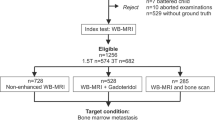

Study inclusion criteria were as follows: CT-guided bone biopsy performed in our department between 01/03/2013 and 28/02/2021, availability of the biopsy CT (Bx-CT) allowing for unequivocal identification of the biopsied lesion, availability of the conclusive histopathology result and contemporaneous MRI including DWI, ADC and rFF images performed within 3 months prior to the biopsy. Within the institute’s radiology information system, data of 150 CT-guided bone biopsies performed in the given time interval were identified. Figure 1 visualises the patient recruitment process. In total, 43 CT-guided bone biopsies performed in five female and 38 male patients, mean age 66 ± 7 years, were included. Primary malignancies in declining order were: 36 prostate adenocarcinoma, four breast adenocarcinoma, one B cell lymphoma, one pulmonary squamous cell cancer and one clear renal cell cancer.